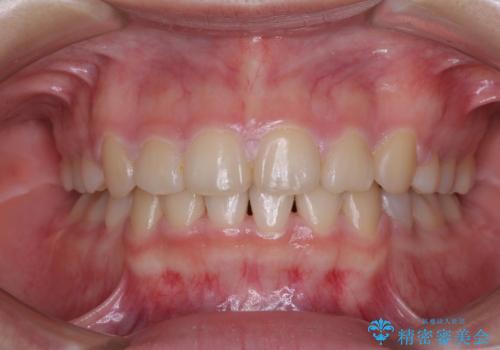

部分矯正を併用した奥歯のインプラント補綴治療

また、残っている最後方歯は手前に倒れてきていたため、部分矯正により奥に移動させてから、インプラント埋入を行うこととしました。

部分矯正期間中はアンカースクリューやフック、ゴムなどが粘膜にあたり、大変な思いをすることになりましたが、そのおかげでインプラント補綴した歯と最後方歯の位置が非常に良好となり、まるでご自身の歯のように咬むことができるようになりました。